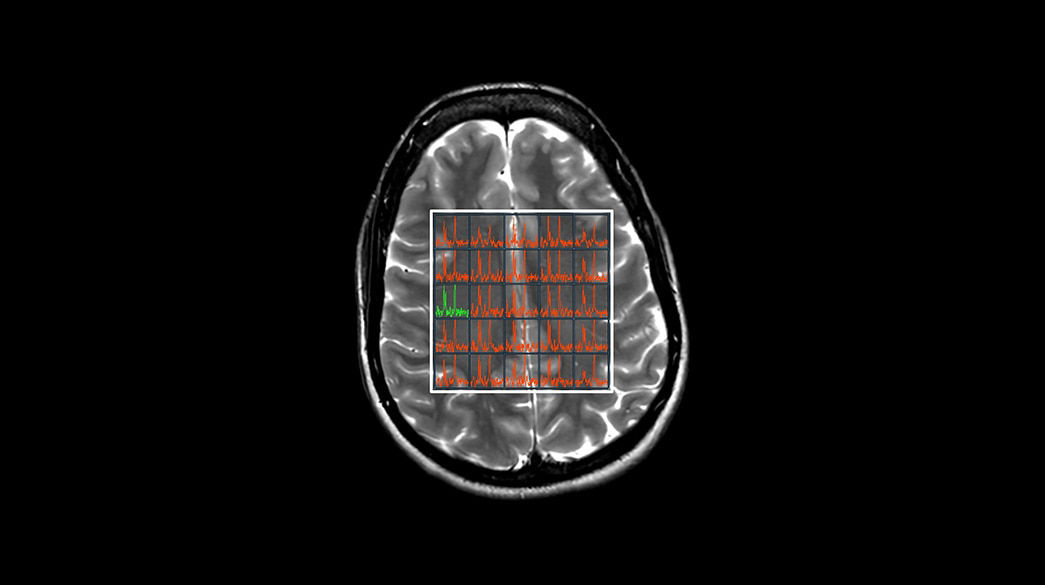

Quantifiable

Provides quantitative and actionable information

Fast

Advanced acceleration techniques for fast and reliable exams